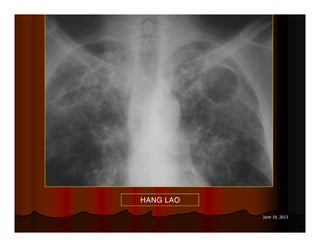

HANG LAO